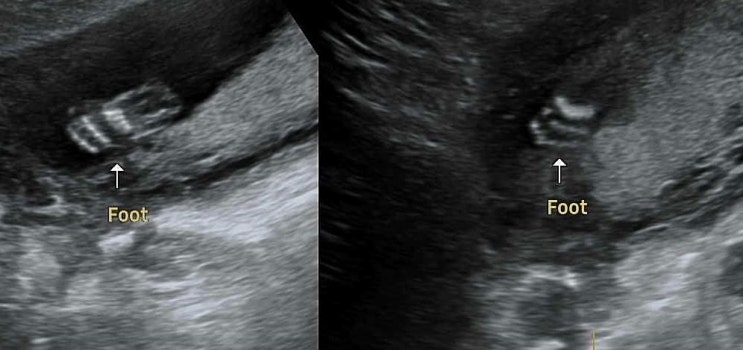

배땡김, 복통으로 산부인과 방문 feat. 19주 초음파

큰 이슈 없이 정기검진으로만 병원을 방문하면 좋으련만... 아침부터 이유 모를 복통과 배땡김, 불편함으로...